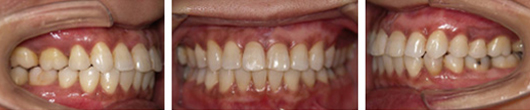

治療前-治療後

初診時の口腔内写真では左の咬合平面が下がっていました。

治療後はきれいに整っています。

左上下顎臼歯部に著しい叢生があり、下顎臼歯部が大きく舌側へ傾斜していました。左はもちろん、右側も歯並びが崩れていて、右ではほとんど咬んでいなかったそうです。